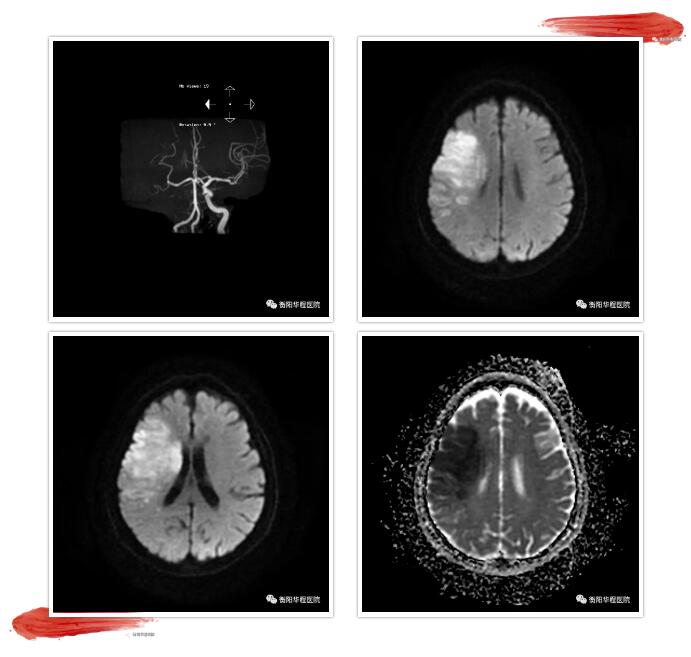

此刻,時間就是大腦,從接診病人、問病史、體格檢查、完善相關(guān)檢查、談話溝通交待病情到開始靜脈注射阿替普酶只用了短短15分鐘。溶栓治療后該患者在我科搶救病房施行持續(xù)神經(jīng)重癥監(jiān)護(hù),入院第二天完善頭部MRI+DWI+MRA+SWI可見顱內(nèi)梗死病灶范圍散在,且未見微出血病灶,證實此次溶栓治療安全有效。該例急性腦梗死患者,是我院我科使用阿替普酶靜脈溶栓第一例,也是我院急診科及我科醫(yī)護(hù)人員奮力為急性腦卒中患者開通生命綠色通道的努力成果。